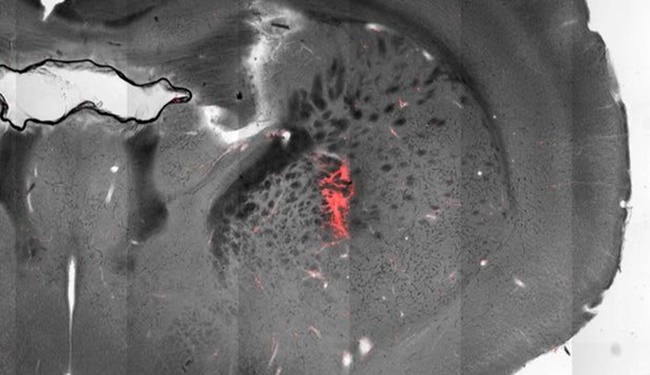

Manyeto termal stimülasyon için genetik açıdan nöronları sıcaklık duyarlı iyon kanalı üretebilen fareler tasarlandı. Sonrasında beynin bu bölgelerine nanoparçacıklar enjekte edilince, nöronlara tutundular. Sonrasında kobalt-ferrit çekirdek mangan ferrit ile kaplandı ve değişen manyetik alan uygulandı .Böylece geri ve ileri manyetizasyon sağlanarak ısınma gerçekleşti.

Bu iyon kanallarının açılmasına neden olarak spesifik nöronların ateşlenmesine neden oldu. “Bu metot sayesinde 100 mikrometre uzunluğunda yaklaşık saç teli kalınlığına çok küçük bir grup hücresini hedef alabiliyoruz,” diyor araştırma lideri Arnd Pralle. Ekip farelerde üç farklı bölümü hedef alarak hareketleri yönetmeyi başardı. Eğer motor korteks uyarılırsa, fare koşmaya başlıyor.